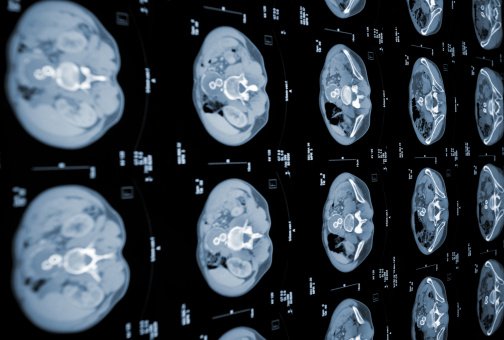

초음파 검사를 통해 췌장의 부종, 낭종, 담석을 확인할 수 있으며, 복부 컴퓨터단층촬영(CT)을 통해서 췌장의 상태와 주변 장기의 상태를 보며 췌장염과 합병증 진단을 할 수 있습니다.